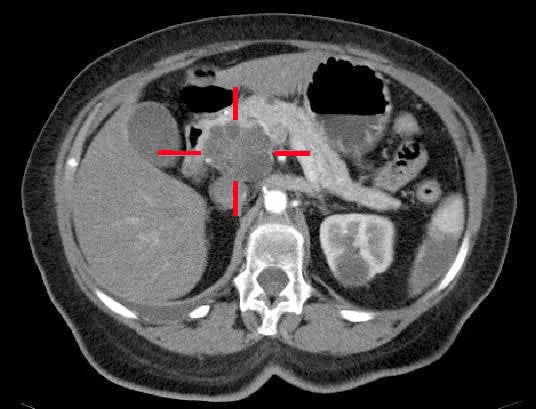

Un adénocarcinome kystique de la tête du pancréas, sur une coupe faite au scanner